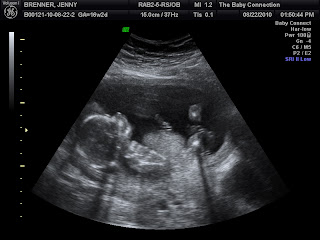

18 WEEKS

I am a few weeks ahead of this now Im hoping to get caught up blogging very soon! I also need to take some new prego pics. The most recent ones I have are not appropriate for the blog or FB. The belly is growing, that is for sure!

I have had 4 ultrasounds!! 4 yes you heard me right 4! I'm 20 weeks along. Do any of you recall seeing any of the Ultrasound pictures? (Other than on Facebook) Nope not a one. I haven't posted one. Do any of you recall me announcing that we are having a baby girl? (Other than on Facebook) Nope. Forgot to do that too. AND apparently when you think of my belly you picture me at 13 weeks right? YEP! since that is the ONLY belly pic I have posted on here. 13 weeks. I'm 20 weeks now. Maybe I should get caught up.

A glimpse at our Monkey....

This is when we discovered you were a little precious girl. I have to say Daddy was REALLY hoping for a boy. You see, that big sister of yours, she is quite the handful from the time she was in my belly until now. The Dr.'s would always tell me how feisty she was. I was always proud to hear that. I was also not thinking about my future with that feisty little baby. She has kept us on our toes every day since. But that is for another post.  That was one of the reasons Daddy wanted a boy. I also secretly wanted a boy in the beginning when we first found out. Then my preference changed, I wanted that feisty sister of yours to have a sister to enjoy everything about have a sister. I sort of knew you were going to be a girl, but I had to keep quite because I wanted someone else to deliver the news to your Daddy. He is ok with it now.  Girls are very special to their Daddy's. I can explain it. You will see. You will have him wrapped around your little finger just like your sister does.

I am excited to discover what you are like. What you look like what your personality is like. Im anxious. You are much different in my belly then your sister was. When the Dr. looks for your heartbeat you comply. No fuss, just there. During your ultrasound you were nestled all up to Mommy. They lady wanted to make you mad so you would move around a little bit so she had me roll over. You would just readjust yourself and get all cozy. I wonder if this is a little sign of your personality. Just easy going. Im so excited to meet you, but you stay in there in get big and healthy for your grand entrance to our Life. We will anxiously wait for you.

Your Mommy